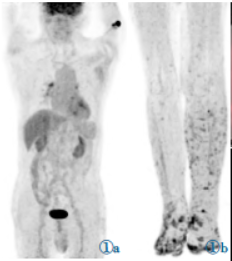

18F-FDG剂量为6.73mCi,注射后1h检查。PET/CT图像采集包括CT平扫和PET扫描。CT扫描参数:电压120keV,电流自动毫安秒,螺距0.6,层厚5mm。PET扫描,2min/床位。扫描范围颅顶至足底。图像采用CT扫描数据衰减矫正,图像重建采用有序子集最大期望迭代法。18F-FDGPET/CT显像示双肺见多发不规则结节,沿肺纹理分布,最大约10mm×15mm,轻度代谢增高,SUVmax为1.9,气管血管旁间质增厚;双下肢皮肤多发不规则结节状增厚,双足多见,代谢异常增高,SUVmax为8.0,伴双下肢水肿(图1)。

图1 18F-FDGPET/CT显像图。图1a,1b为体部及下肢MIP图,下肢见多发异常高代谢结节;图1c,1d见双肺多发结节,大部分形态不规则,沿肺纹理分布,轻度代谢;图1e,1f见双足皮肤多发不规则、结节状增厚,代谢异常增高。